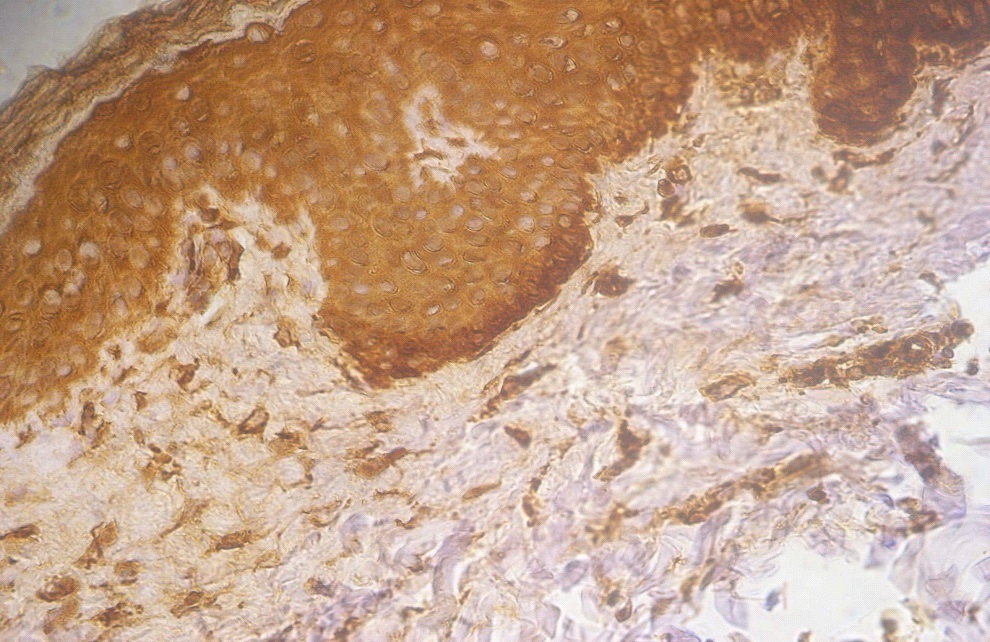

Figure 3. +3 dermal PGP9.5 positive staining in a lesional non segmental Vitiligo case (immunohistochemical stain, x400)

Among the lesional biobsies there were 3 patients (15%) with +2 and 17 patients (85%) with +3 positivity staining for  PGP9.5,  while in the non lesional ones there were 11 patients (55%) with +1 and 9 patients (45%) with +2 positivity staining for PGP9.5. Lesional biopsies also showed that there were 12 patients (60%) with +2 and 8 patients (40%) with +3 positivity staining for ssDNA and the  non lesional ones showed 18 patients (90%) with +1 and 2 patients (10%) +2 staining for ssDNA (Table 1 and Figures 1-6).